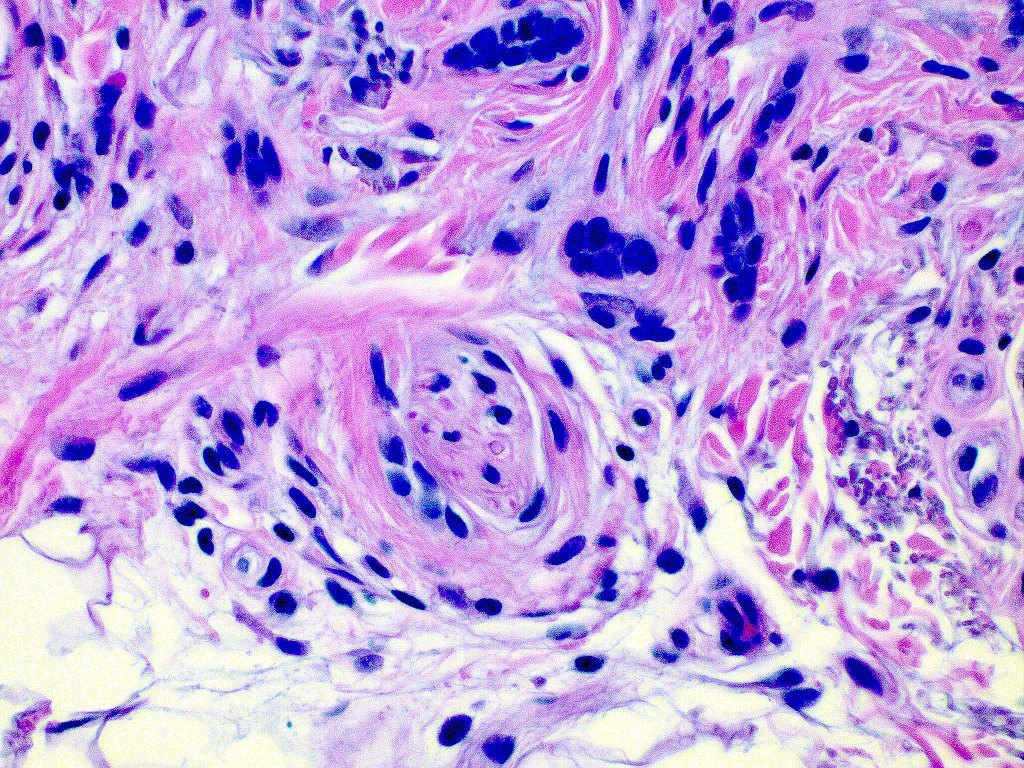

Histological features

•Consists of narrow epithelial strands & keratocysts embedded in a dense stroma

•Generally involves superficial & mid dermis but does not extend into the subcutaneous fat

•No evidence of glandular differentiation

•Calcification, foreign body giant cell reaction to keratin & bone are inconstant findings

•Epithelial stands may arise from follicular epithelium

•Can rarely see matricial differentiation

•Perineural infiltration is documented but is exceptional & makes differentiation from MAC difficult

•Co-existence with a dermal nevus is sometimes encountered